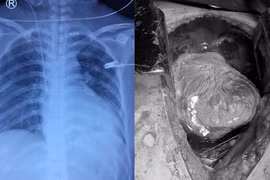

Trong quá trình phẫu thuật, kíp mổ phát hiện bệnh nhân bị vết dao đâm thấu nhĩ phải tim, đứt động mạch ngực trong bên phải khiến máu tràn ra khoang màng phổi phải và khoang ngoài tim.